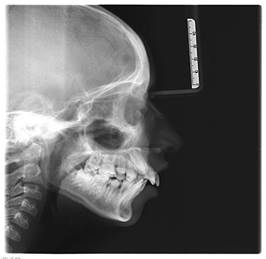

In the Lavergne and Petrovick cephalometry, performed taking the lateral cephalograms as a reference (Figure 4), the patient has shown neutral mandibular rotation, maxilla larger than the mandible, a distal anteroposterior relation with a normal vertical relation (R2DN).

Figure 4: Lateral cephalogram showing proinclination of upper incisors and decreased mandibular length

The cephalometric study showed the following:

- A retrognathic profile

- Mandibular retrognathism

- Clockwise jaw rotation

- Vertical growth

- Dental and skeletal Class II

- Short mandibular length

- Dolichofacial type

- Proinclined and protruded upper incisors

- Increased overjet and overbite

- Deep bite